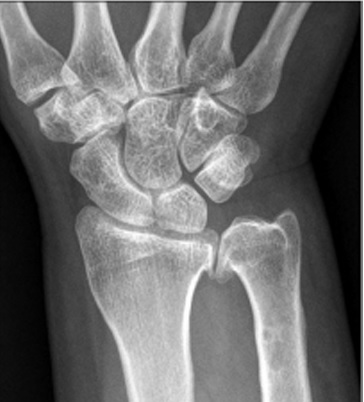

In uw pols is in het gewricht tussen het spaakbeen en ellepijp (het DRUJ) artrose ontstaan. De oorzaken hiervoor zijn: niet anatomisch geheelde fracturen van de pols, (onbehandelde) bandletsels van de pols, instabiliteit, kraakbeenslijtage, reuma of groeiafwijkingen (Madelung) van de pols.

Een radiografie van een pols met DRUJ arthrose